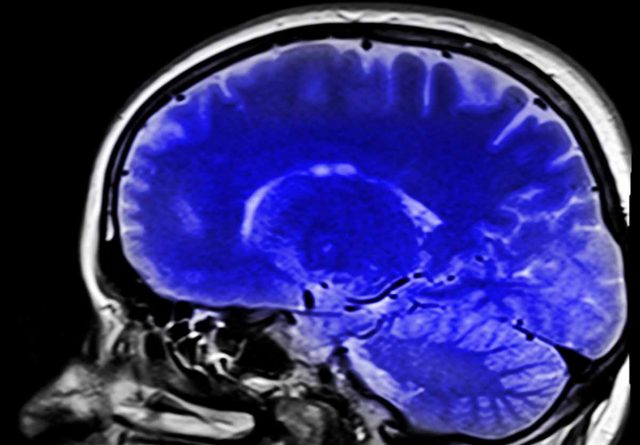

Dapatkah Sains Menjelaskan Tentang Kesadaran?

Hingga kini sains belum bisa menjelaskan bagaimana kesadaran (consciousness) bisa terbentuk di dalam otak kita. Otak manusia adalah organ manusia yang luar biasa kompleks, terdiri dari hampir 100 milyar sel, ysng dikenal dengan neuron, dan setiap satu sel dapat terhubung dengan 10.000 sel lainnya, membentuk sekitar 10 triliun sambungan saraf. Hingga kini, sains telah mencapai kemajuan yang pesat dalam memahami...